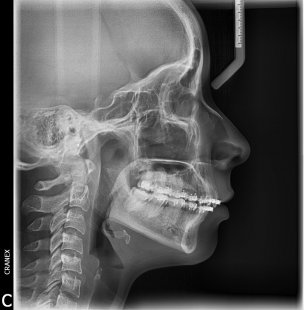

- RX .Lateral Estricta

- RX. Lateral en posición natural de la cabeza (PNC)

- RX .Lateral 7ma vertebra